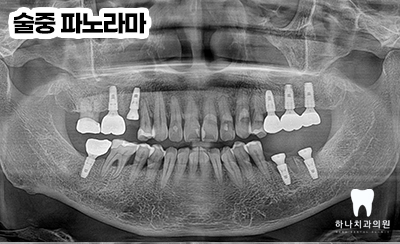

큰 문제 없이 필요한 자리에

임플란트 수술 후 뼈이식을 실시하였습니다.

재수술 과정에서는 디지털 영상 진단 장비를

활용하여 기존 임플란트 주변의 뼈 상태와

염증 유무, 식립 각도 등을 정밀 분석하는 것이

일반적으로 이를 통해 오차를 최소화하고

환자별 구강 구조에 적합한 치료 방법을 적용할 수 있습니다.